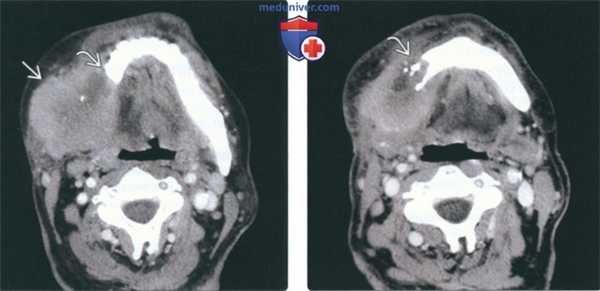

(Слева) На аксиальной КТ с КУ в жевательном пространстве справа визуализируется злокачественная фиброзная гистиоцитома нижней челюсти в виде минимально контрастирующегося солидного объемного образования, разрушающего ветвь и тело нижней челюсти. Жевательное пространство является известным местом возникновения сарком глубоких областей ли ца.

(Справа) На аксиальной КТ с КУ у этого же пациента визуализируется опухоль в жевательном пространстве справа, приводящая к обширной деструкции нижней челюсти. Обратите внимание на асимметрию лица на стороне поражения.2. КТ при саркоме жевательного пространства:

(Слева) КТ с КУ, аксиальная проекция. Злокачественная фиброзная гистиоцитома жевательного пространства и нижней челюсти. Солидная опухоль, которая умеренно накапливает контраст, располагается в правом жевательном пространстве и разрушает нижнюю челюсть, в том числе ее ветвь и тело. Жевательное пространство представляет собой глубокую область лица, в которой может возникать саркома.

(Справа) КТ с КУ, аксиальная проекция, тот же пациент. Солидная опухоль, умеренно накапливающая контраст, разрушает значительную часть нижней челюсти.2. КТ при саркоме жевательного пространства: